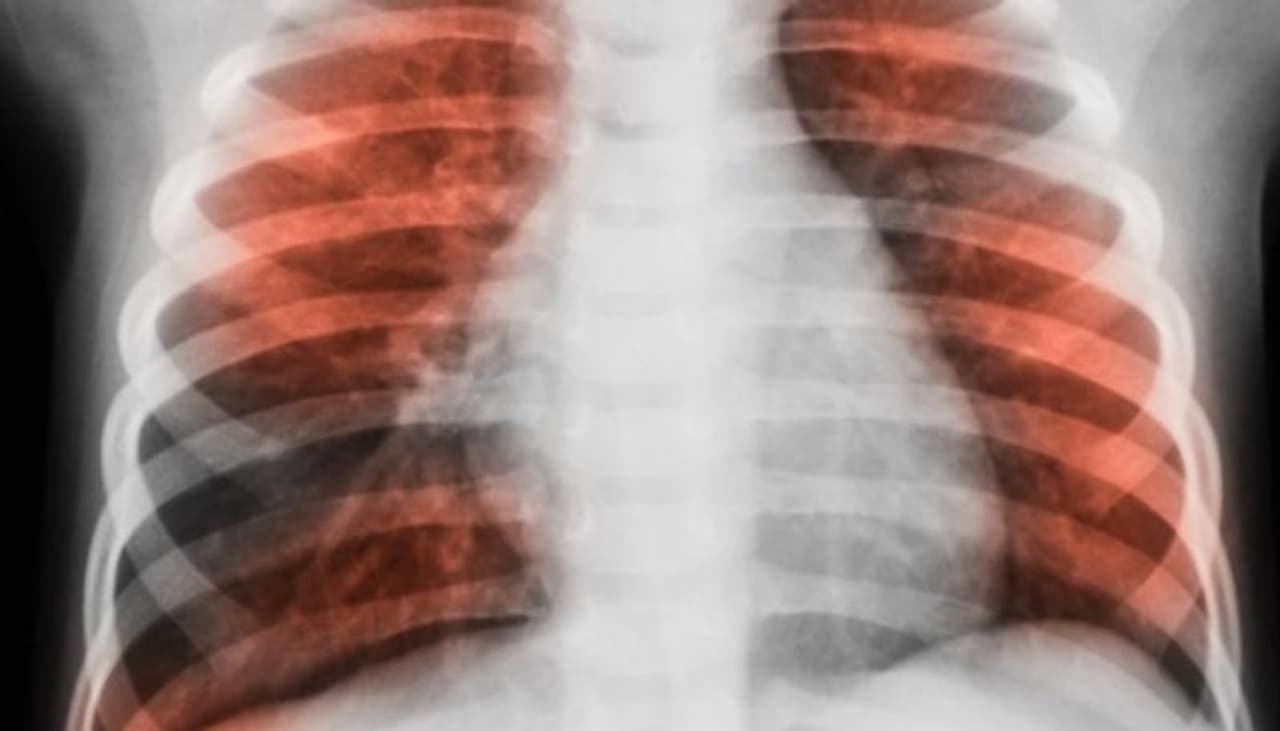

സാധാരണഗതിയില് നമ്മളെല്ലാം ഈ ഫംഗസിനെ ശ്വസനത്തിലൂടെ അകത്തെടുക്കാന് സാധ്യതയുള്ളതാണെന്നാണ് വിദഗ്ധര് പറയുന്നത്. എന്നാല് പ്രതിരോധശേഷി വളരെ കുറവായവരാണെങ്കില് അവര് ഈ ഫംഗസിനെ അകത്തേക്കെടുക്കുമ്പോള് അത് 'ആസ്പെര്ജിലോസിസ്' എന്ന ഫംഗല് ബാധയ്ക്ക് കാരണമാകുന്നു. ശ്വാസകോശത്തിലാണ് പ്രധാനമായും അണുബാധയുടെ പ്രശ്നങ്ങളുണ്ടാക്കുക എന്നതിനാല് തന്നെ നേരത്തേ ശ്വാസകോശ രോഗമുള്ളവരിലും രോഗം വരാനുള്ള സാധ്യത കൂടുതലാണ്.